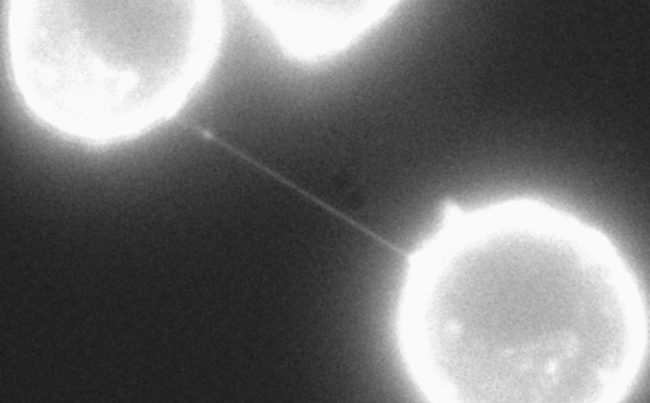

Člani ameriške raziskovalne skupine so preučevali interakcije med rakavimi in imunskimi celicami, pri tem pa so celice raka dojke inkubirali skupaj z različnimi imunskimi celicami. Z elektronsko mikroskopijo so opazili, da so bile rakave in imunske celice po skupni inkubaciji fizično povezane s cevkami, ki v premeru meriju nekaj nanometrov.

Razne celice si lahko po tovrstnih nanocevkah izmenjujejo snovi, pa tudi organele. Predhodno je bilo pokazano, da si celice povrhnjice po takih cevkah izmenjujejo tudi mitohondrije, ki celice preskrbujejo z energijo. Pri nekaterih rakih je bila opažena povezava med povečanjem števila mitohondrijev in napredovanjem tumorja ter razvojem odpornosti proti kemoterapiji. Zato so znanstvenice in znanstveniki mitohondrije v imunskih celicah obarvali s fluorescenčnim barvilom, nato pa so jih inkubirali skupaj z rakavimi celicami. Po nekaj urah so fluorescenčni signal opazili tudi v rakavih celicah. V nadaljevanju raziskave so obarvali mitohondrije v rakavih celicah. Mitohondriji so le redko potovali v nasprotni smeri, torej iz rakavih celic v imunske. To nakazuje, da je potovanje mitohondrijev pretežno enosmerno, in sicer iz imunskih celic v tumorske.